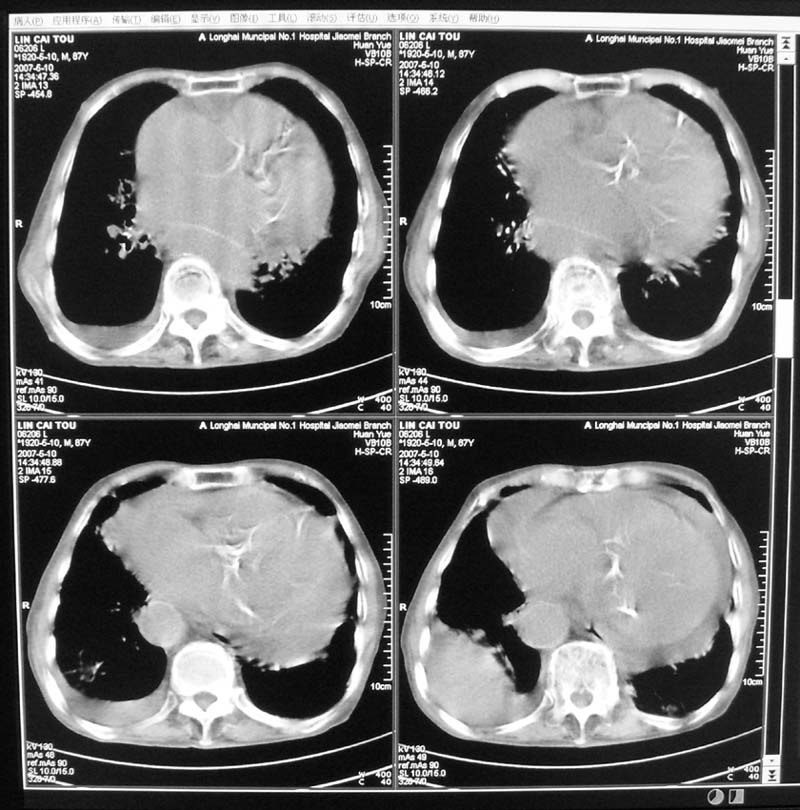

以下是引用小初学者在2007-5-12 16:26:00的发言:[br]1、心衰肺水肿两侧胸腔积液2、心包积液3、心瓣膜钙化